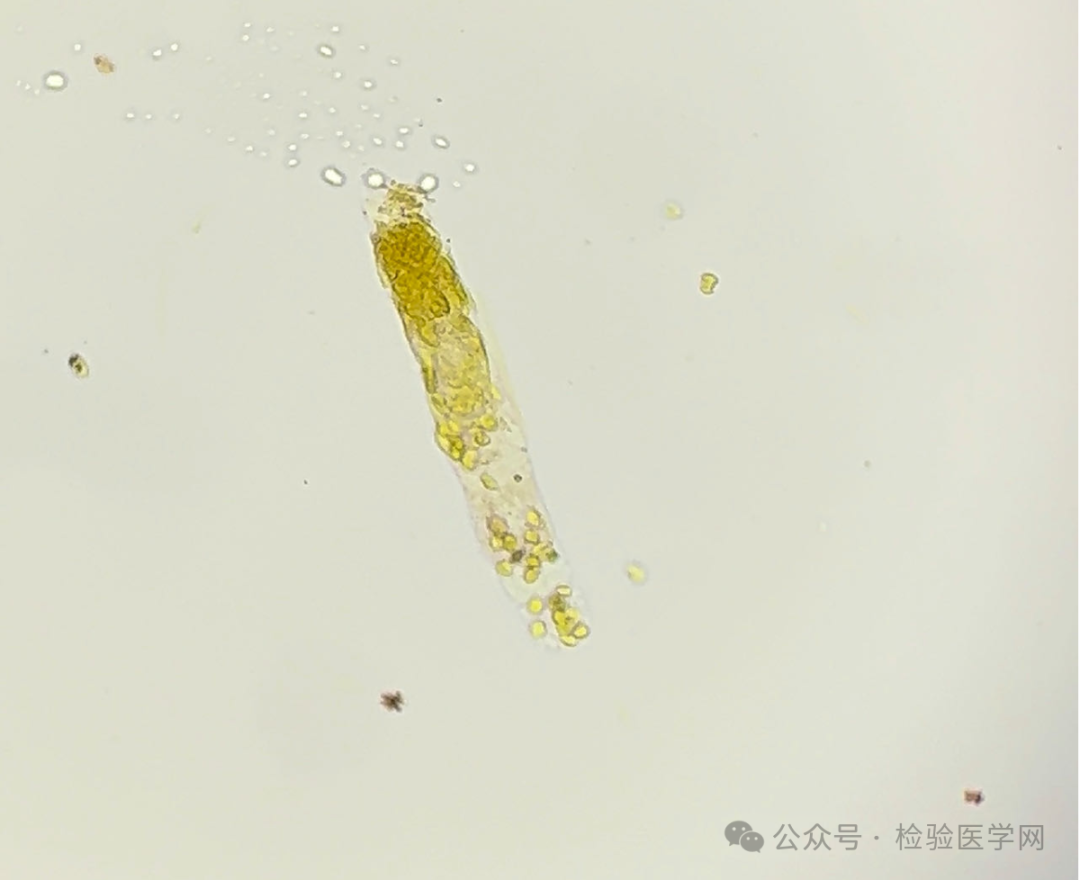

胆红素结晶管型

(尿液 未染色400倍)